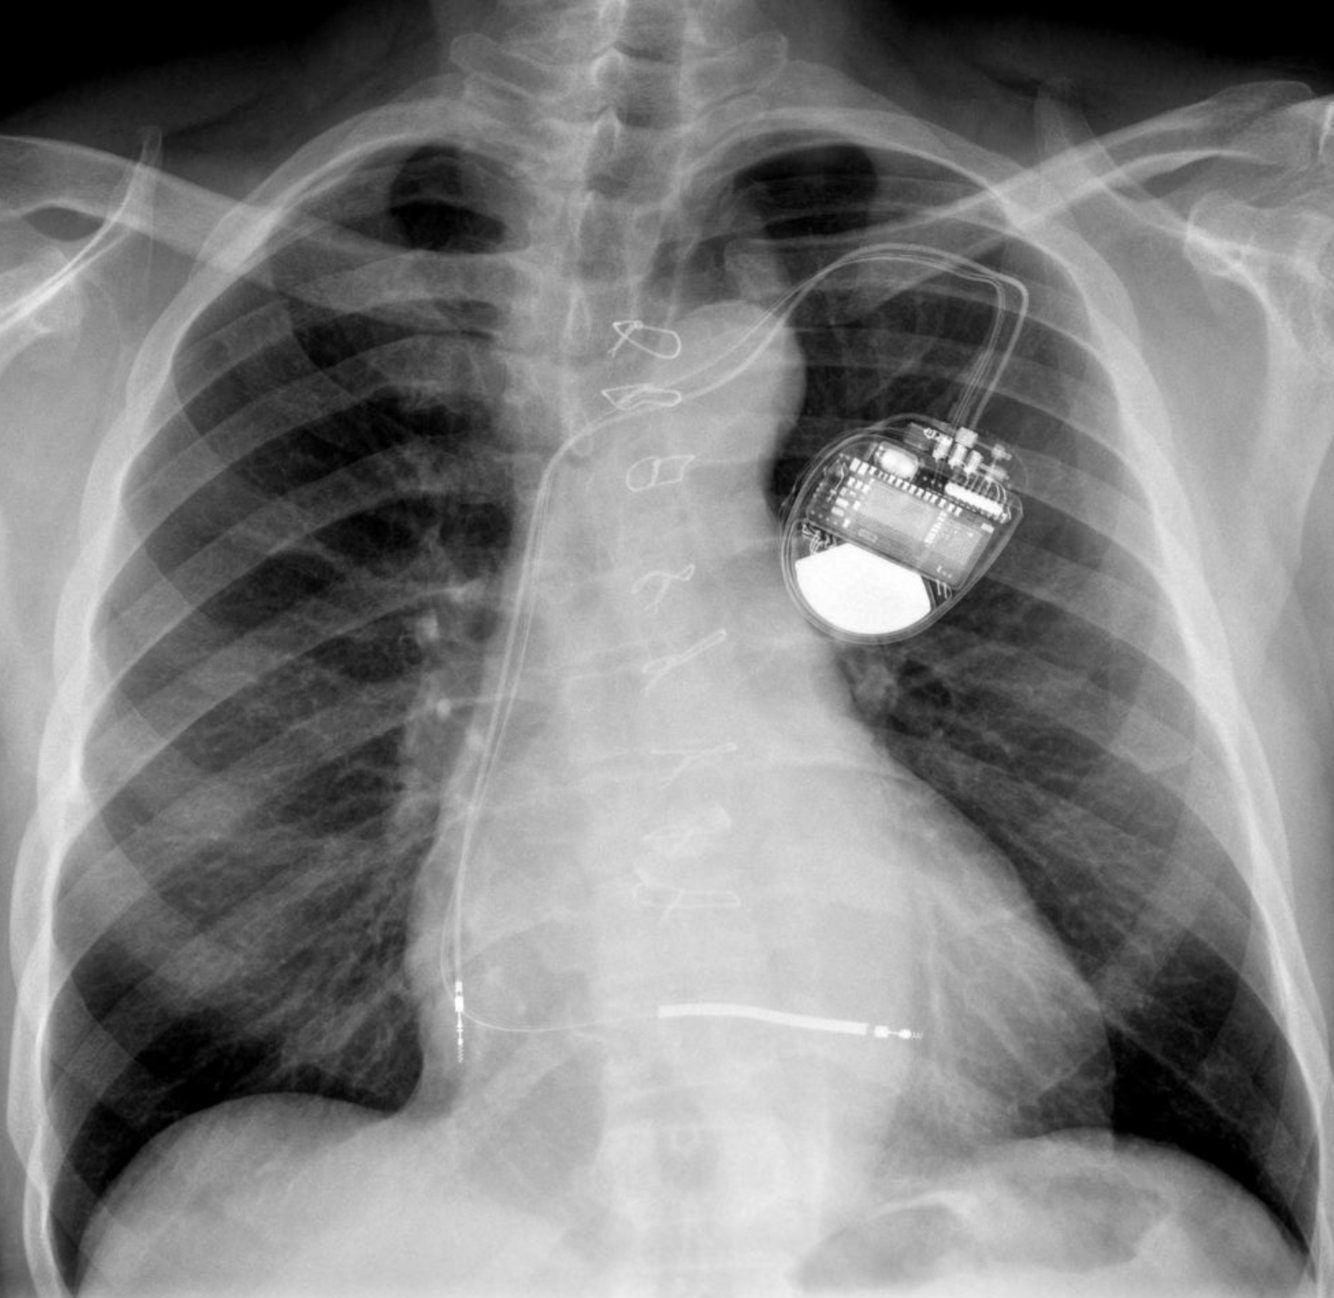

8

Q

A

-LAA Occluder device

-Sternotomy clips

-Dual chamber pacemaker

How well did you know this?